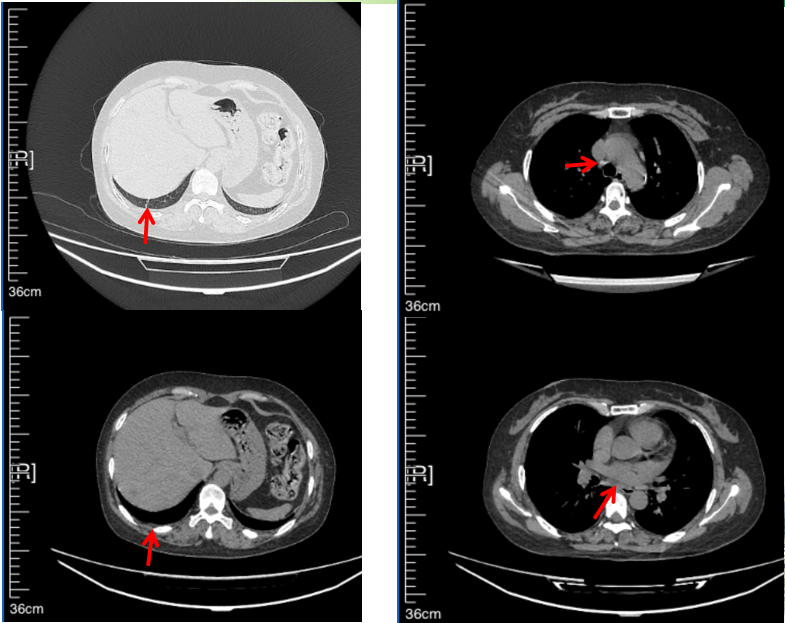

2016年1月复查CT提示支气管截断可见新发小结节,一线治疗采用培美曲塞+DDP方案化疗4周期(培美曲塞3.36,DDP 480mg)。化疗后复查胸部CT:右肺见不规则结节样影,最大层面大小约19mm*8mm,较前比较明显增大,疗效评估PD。2017.3-2017.4予单药多西他赛化疗3周期,疗效评估SD。2018年5月末复查CT提示结节较前增大,评效为PD,2018年6-10月予多西他赛+CBP化疗4周期,疗效评估SD。2022年5月患者出现活动后气短,复查胸部CT示右肺膨胀不良;右侧胸腔积液增多。胸腔积液包埋病理示符合肺腺癌细胞。行NGS基因检测:EML4:exon13-ALK:exon20融合。PD-L1(克隆号22C3)TPS<1%。

临床诊断:右肺上叶恶性肿瘤rT0N0M1a IVA期(第9版分期);恶性胸腔积液。

诊疗经过:2022年5月始口服克唑替尼3个月,出现肝功能异常(DILI 2级伴临床症状),改用恩沙替尼靶向治疗至今,目前评效为维持PR。恩沙替尼应用期间出现轻度肝功能异常(DILI 1级),对症处理后好转。截止目前PFS 33个月。

2018.07

2022.05

2024.12